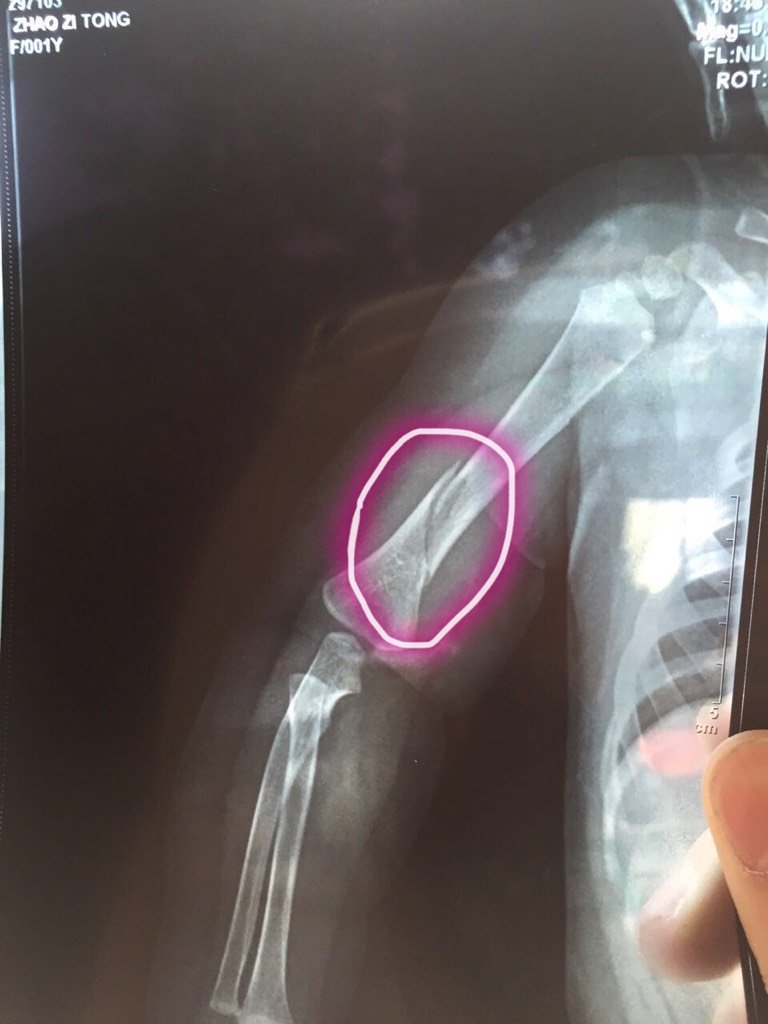

我女儿九个月胳膊骨折 从椅子上倒下来胳膊骨折了 你们看能不能长好 有什么办法吗 我女儿九个月胳膊骨折 从椅子上倒下来胳膊骨折了 你们看能不能长好 有什么办法吗 点击展开 小心肝💋 2016-06-14 16:43 为您推荐: 其他回答 。z z z z YYMM 2016-06-14 23:13 咨询医生!看医生怎么说呗 喜扬扬妈咪 2016-06-14 22:30 祝宝宝早日康复 158*****954_fmIg 2016-06-14 21:52 去医院看看 安啦贝比 2016-06-14 18:54 能长好的,要打石膏 151*****606_eNWa 2016-06-14 17:56 加载更多 相关问题 我女儿九个月 从椅子上倒下来胳膊骨折 小孩子在学校,老师叫同学去搬椅子,两个小孩把另外一个不小心把胳膊弄骨折了,学校有责任吗? 小孩子从椅子捽上捽下看医生说是骨折,但是X光片又看不懂